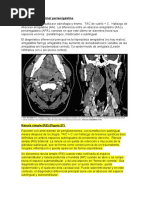

Figura 9: Adenopata cervical. (a): Masa en la regin superior del cuello (b). TAC de la masa: Linfoma

8.